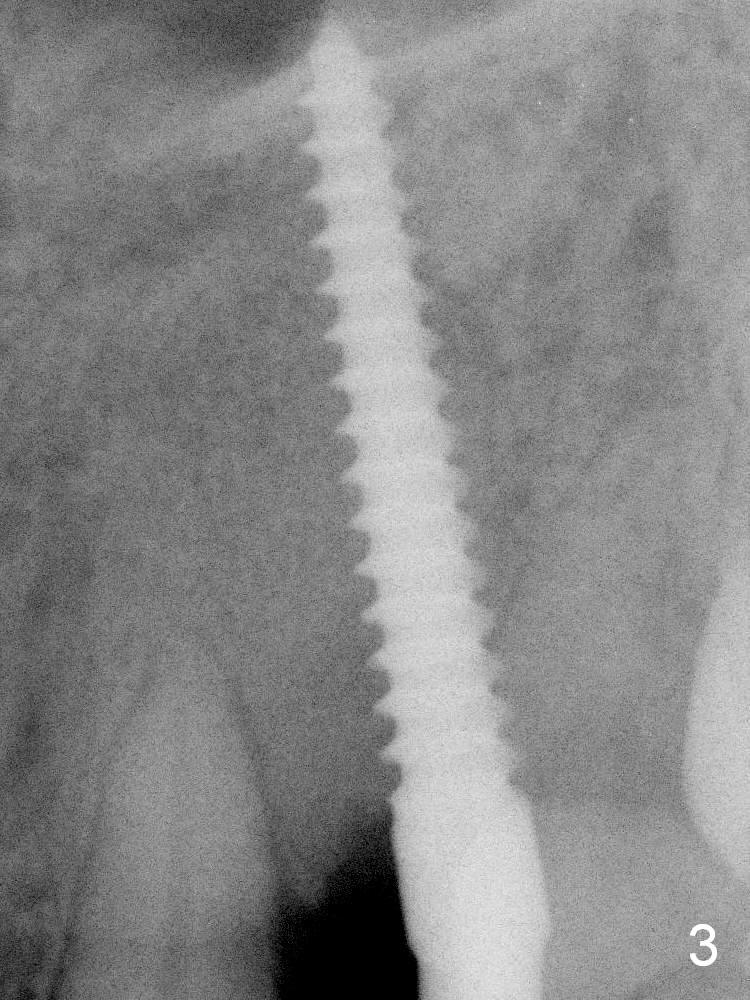

Intraop PA shows that the nasal floor is apparently perforated (Fig.3). In fact the transverse cortical plate is the horizontal plate of the palatine bone.